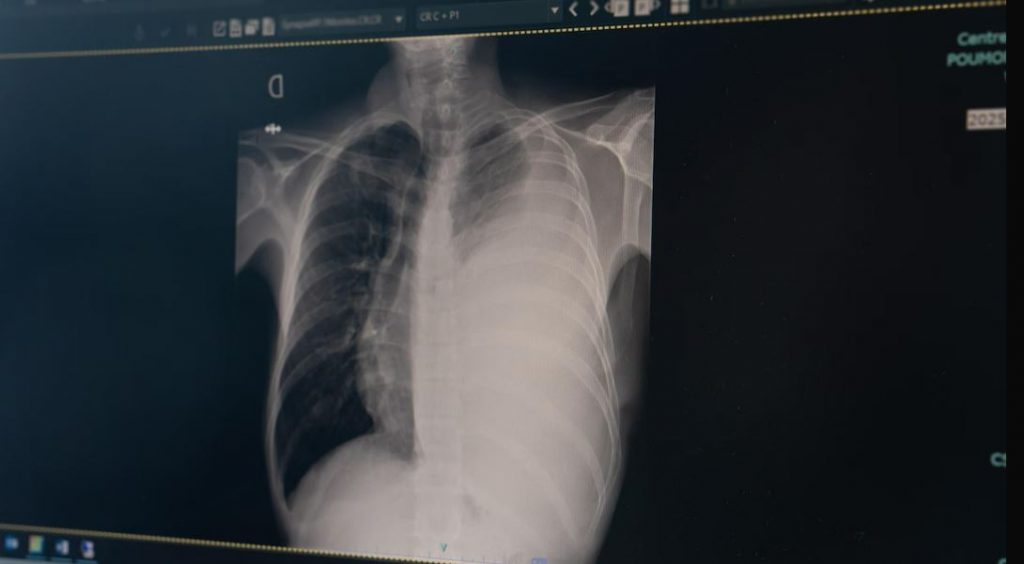

La Croix-Rouge canadienne (CRC) viendra prêter main-forte aux autorités de santé publique dans la lutte contre la tuberculose au Nunavik, dans le Nord-du-Québec, alors que la maladie a atteint un niveau de transmission inégalé dans la région au cours de la dernière année.

En 2025, il y avait 117 cas de tuberculose actifs au Nunavik, un record. À la mi-février, 13 cas avaient déjà été signalés par les autorités de santé publique depuis le début de l’année.